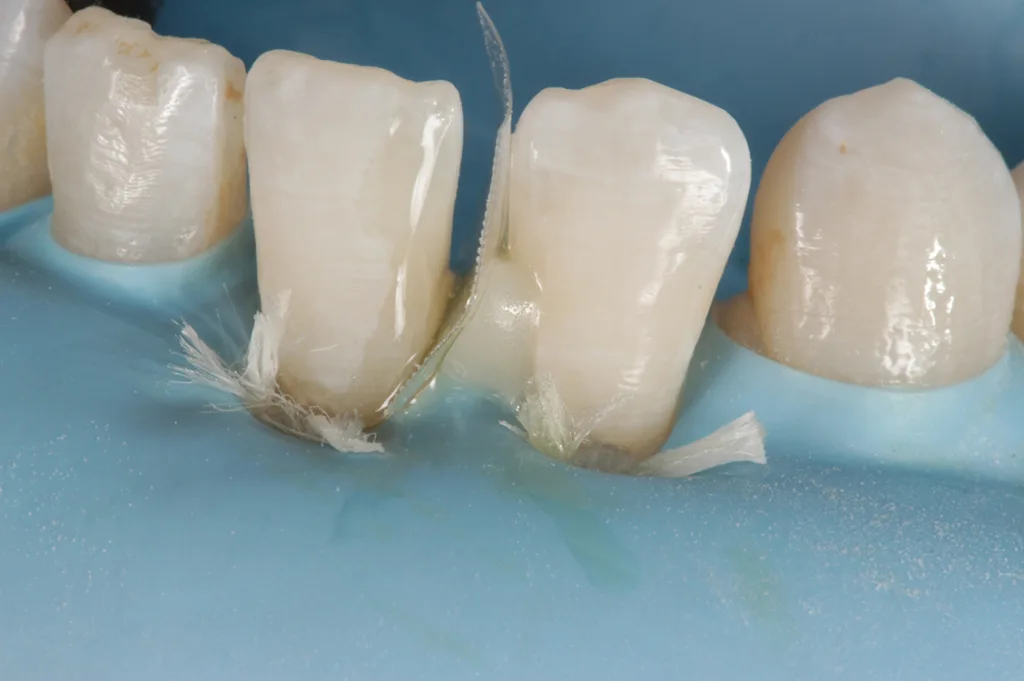

Nach Befundaufnahme und professioneller Zahnreinigung wurde ein CMD-Kurzscreening durchgeführt und ein Fotostatus erstellt. Ein intraorales Mock-up [2] wurde auf Wunsch der Patientin und aus Kostengründen nicht angefertigt. Definitive Versorgung Adhäsivrestaurationen mit Komposit an 31/32 zum Schluss des Diastema laterale (Abb. 3 bis 9).

Es zeigen sich postoperativ leichte Irritationen der Gingiva, die durch das Legen der Retraktionsfäden/Ligaturen entstanden sind und sich nach Abheilung und Reifung im Interdentalbereich noch adäquat ausformen werden, um somit einem ansprechenden dentogingivalen Erscheinungsbild zu entsprechen.